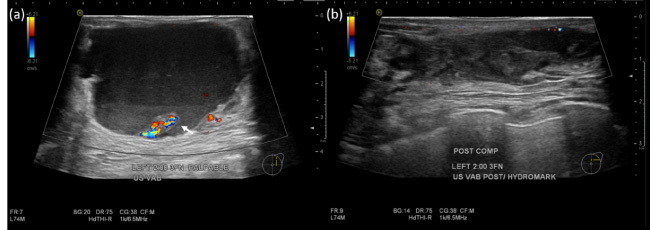

An 85-year-old Chinese lady presented with a 5-day history of a painless left breast lump. There was no fever, nipple discharge, or history of trauma. She had a past medical history of atrial fibrillation that was managed with an oral anticoagulant. Mammography demonstrated a dense mass in the upper outer quadrant of the left breast. Ultrasound showed an irregular, heterogeneous 4.7 cm lesion containing debris and cystic spaces with raised peripheral vascularity at the 2 o'clock position, 3 cm from nipple. No internal vascularity was detected. This was managed as a haematoma and rivaroxaban was withheld. Follow-up imaging 3-weeks later showed persistence of the lesion. Bedside needle aspiration yielded haemoserous fluid with immediate reduction in size of the lesion. However, 2 weeks after aspiration, there was recurrence of the 'haematoma'. Multidisciplinary review of the clinical history, examination and imaging was sought, and biopsy of the irregularly thickened areas with vascularity along the periphery of the lesion was recommended. Vacuum-assisted biopsy was performed, and histology returned as metaplastic carcinoma. A recurring 'haematoma' should always prompt a search for a secondary cause, with features such as irregular thickened walls and papillary/nodular components requiring further evaluation with biopsy for histopathological correlation.